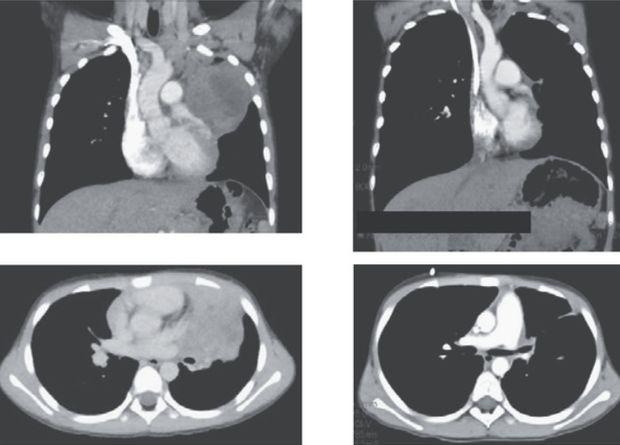

Японские врачи описали два случая, в которых дети «заразились» от матерей раком шейки матки. У обоих мальчиков опухоли выросли в легких — однако и по строению ткани, и генетически были очень похожи на материнские: например, в них не было Y-хромосом. Поэтому исследователи предположили, что передача опухоли произошла во время родов: когда дети проходили через шейку матки, раковые клетки попали к ним в дыхательные пути, а затем поселились и разрослись внутри легких. Отчет опубликован в журнале The New England Journal of Medicine.

У развивающегося ребенка иммунитет еще не работает в полную силу и не может противостоять материнской опухоли. Зато плод отделен от материнского кровотока плацентой, через которую раковым клеткам пробраться непросто. Поэтому такое заражение встречается крайне редко: примерно один раз на 500 тысяч онкобольных матерей. Теперь Аюму Аракава (Ayumu Arakawa) из государственной